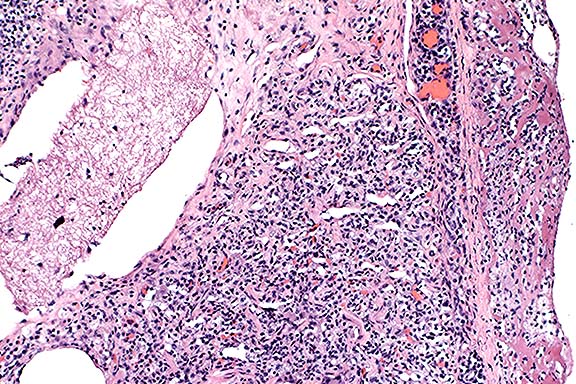

Signalment: 5-year-old, intact female, Brittany Spaniel Canine.

History: This dog had a 6-week history of chronic diarrhea. The diarrhea was fluid and contained some blood. The dog was non-responsive to treatment and progressively became severely emaciated, hypoproteinemic, hypoalbuminemic and developed a non-regenerative anemia. The dog was euthanized.

Gross Pathology: There was a marked, generalized reduction

in muscle mass and fat stores with serous atrophy of fat. There

was extensive generalized subcutaneous edema and ascites. Hepatomegaly

was marked and the liver was pale, friable and bulged over the

capsular surface when cut. Distributed along the entire length

of the gastrointestinal tract, there were multifocal to coalescing

white nodular transmural firm thickenings (1-5 cm) which had a

smooth serosal surface and multifocal ulcerations of the mucosa.

Similar nodular lesions were present in the adrenal glands (bilateral)

involving both the cortex and medulla and throughout the spleen.

There was generalized enlargement of lymph nodes (5 - 10 X normal)

which were multinodular, mottled white tan and firm. The lungs

were wet, heavy (pulmonary edema) and there were non-discrete,

irregular areas of lung, multifocally involving all lobes which

were pale and firm. They ranged in size from 0.5 cm to

4 cm in diameter.

The wide spread dissemination of the H. capsulatum organism throughout the body resulted in these additional lesions:

3. Severe, chronic, multifocal to coalescing granulomatous

hepatitis with intralesional yeasts (Histoplasma capsulatum).

4. Severe, chronic, diffuse granulomatous lymphadenitis with intralesional

yeasts (Histoplasma capsulatum).

5. Moderate, chronic, multifocal granulomatous pneumonia with

intralesional yeasts (Histoplasma capsulatum).

6. Severe, chronic, multifocal to coalescing granulomatous splenitis

with intralesional yeasts (Histoplasma capsulatum).

Conference Note: Disseminated histoplasmosis causes a variety of clinicopathologic findings. In dogs, hematologic abnormalities often include a leukocytosis resulting from neutrophilia and monocytosis. There may be a left shift. As was seen in this case, a nonregenerative anemia is common, due both to chronic inflammatory disease and to replacement of normal bone marrow elements by Histoplasma-laden histiocytes. Thrombocytopenia has been a variable feature in dogs.

Serum chemistry changes indicating cholestatic liver disease are often found, including increases in serum alkaline phosphatase activity and conjugated bilirubin levels. Serum albumin is often decreased. Alanine aminotransferase is only occasionally increased, due to the infiltrative rather than hepatocellular nature of the disease. Serum globulin concentrations may be normal or increased.